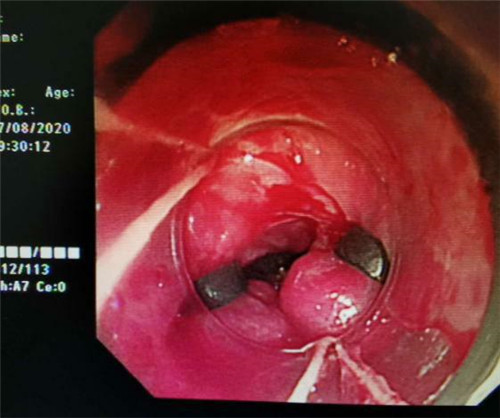

手术中,在镜下发现数条食管静脉曲张延伸至胃底,胃腔内有大量新鲜红色血液及血凝块,寻找到出血部位时仍在向外渗血,血压持续下降,患者时刻有生命危险。曹鹏副主任当机立断对曲张静脉破口处进行组织粘合剂及硬化剂注射,并对曲张静脉进行套扎治疗,在麻醉师陈琦的保驾护航下,整个过程不到半个小时,为患者成功止血,患者转危为安。